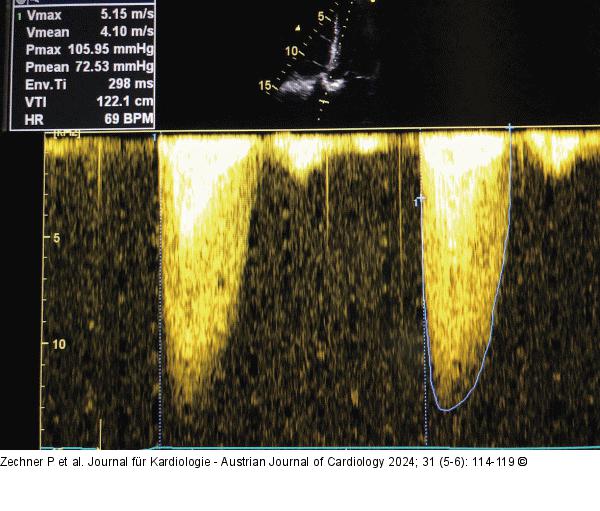

Abbildung 3: CW-Doppler - Overgain CW-Doppler: Aortenklappenstenose vor hellem Hintergrund = „Overgain“. |

CW-Doppler: Aortenklappenstenose vor hellem Hintergrund = „Overgain“. |